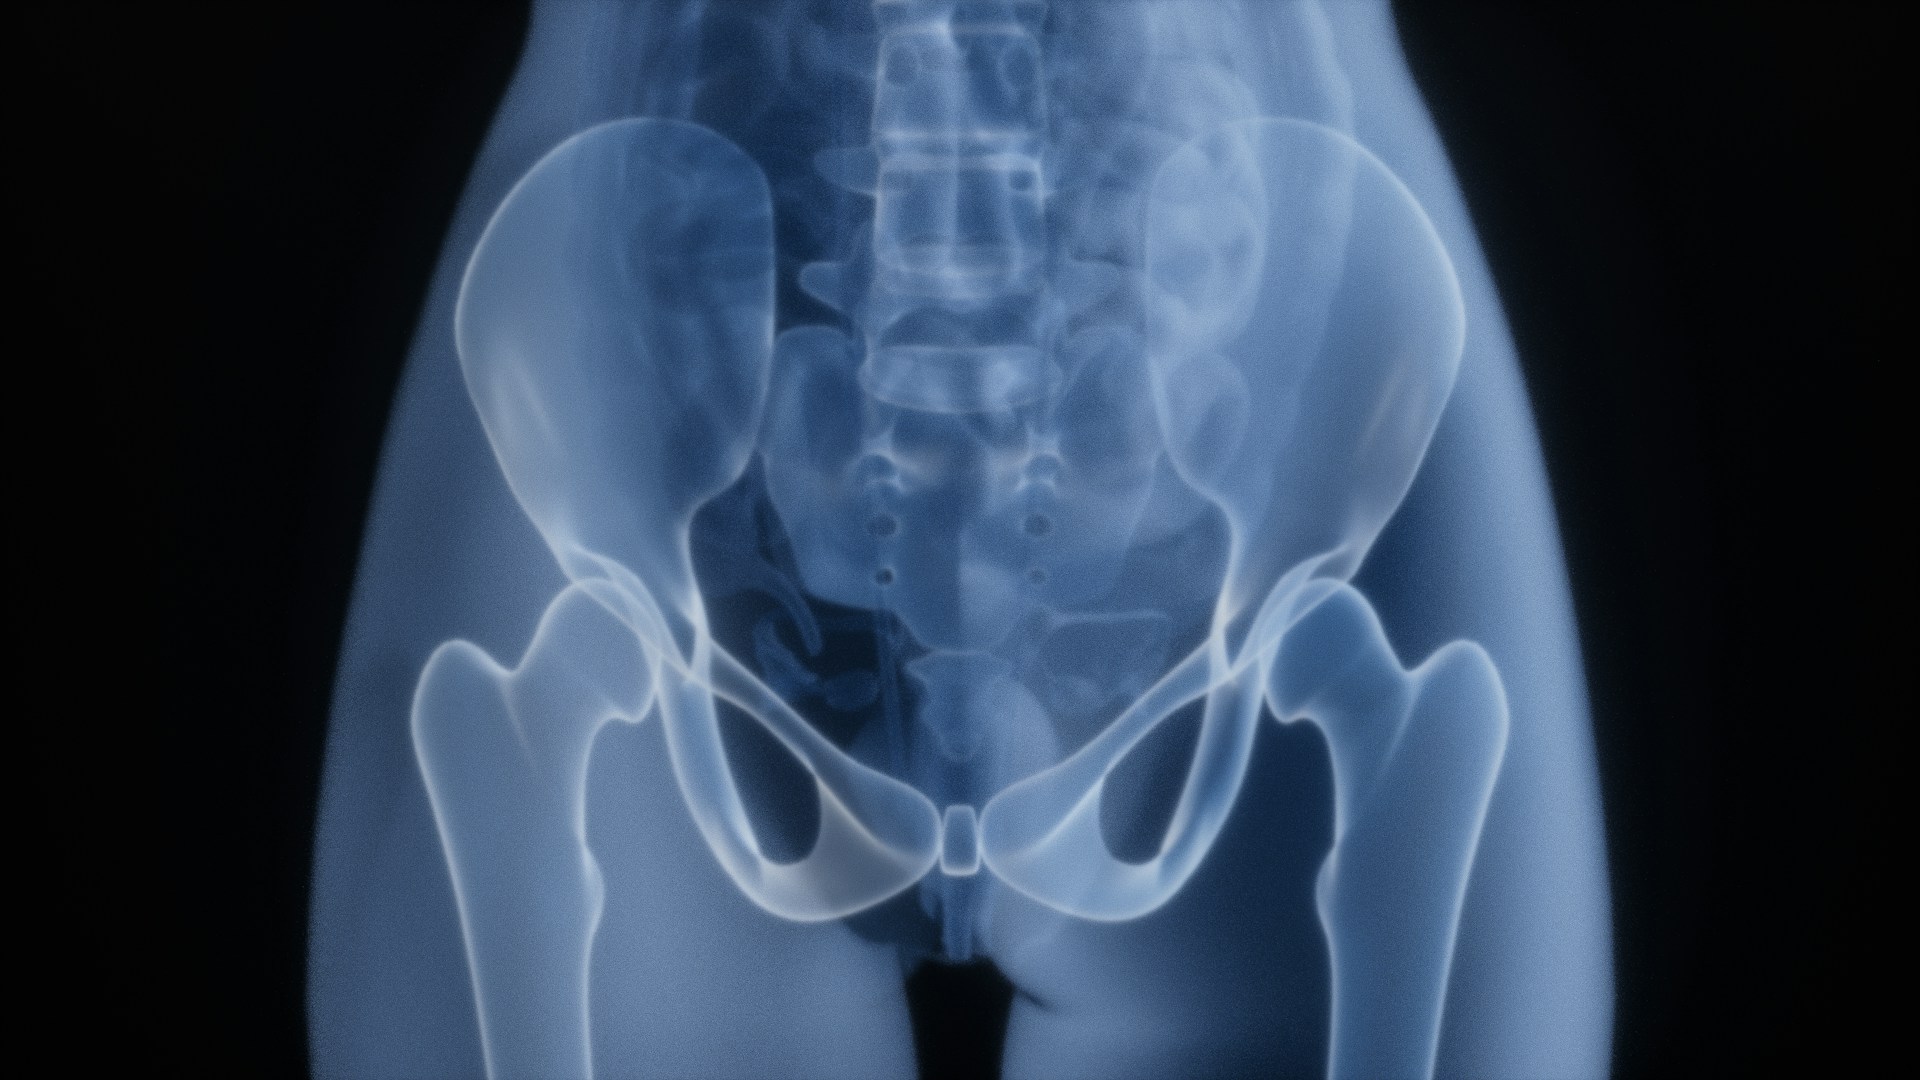

Sciatica occurs when the sciatic nerve — which runs from the lower back through the buttocks and down each leg — becomes irritated. This irritation can cause pain, numbness, tingling, or muscle weakness in the buttock and leg.

Sciatica buttock pain is a common and often debilitating symptom of irritation or compression of the sciatic nerve. The pain can feel sharp, burning, or radiating, making it difficult to sit, walk, or move comfortably. Understanding what causes sciatica buttock pain can help you find the right treatment and prevent the condition from becoming chronic.